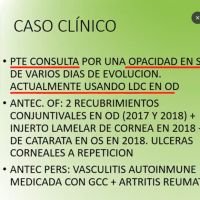

- Florencia Miranda